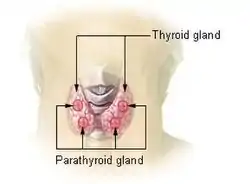

| Above shows two parts of the thyroid that could potentially be affected if diagnosed with thyroiditis. | |

Thyroiditis is the inflammation of the thyroid gland. The thyroid gland is located on the front of the neck below the laryngeal prominence, and makes hormones that control metabolism.